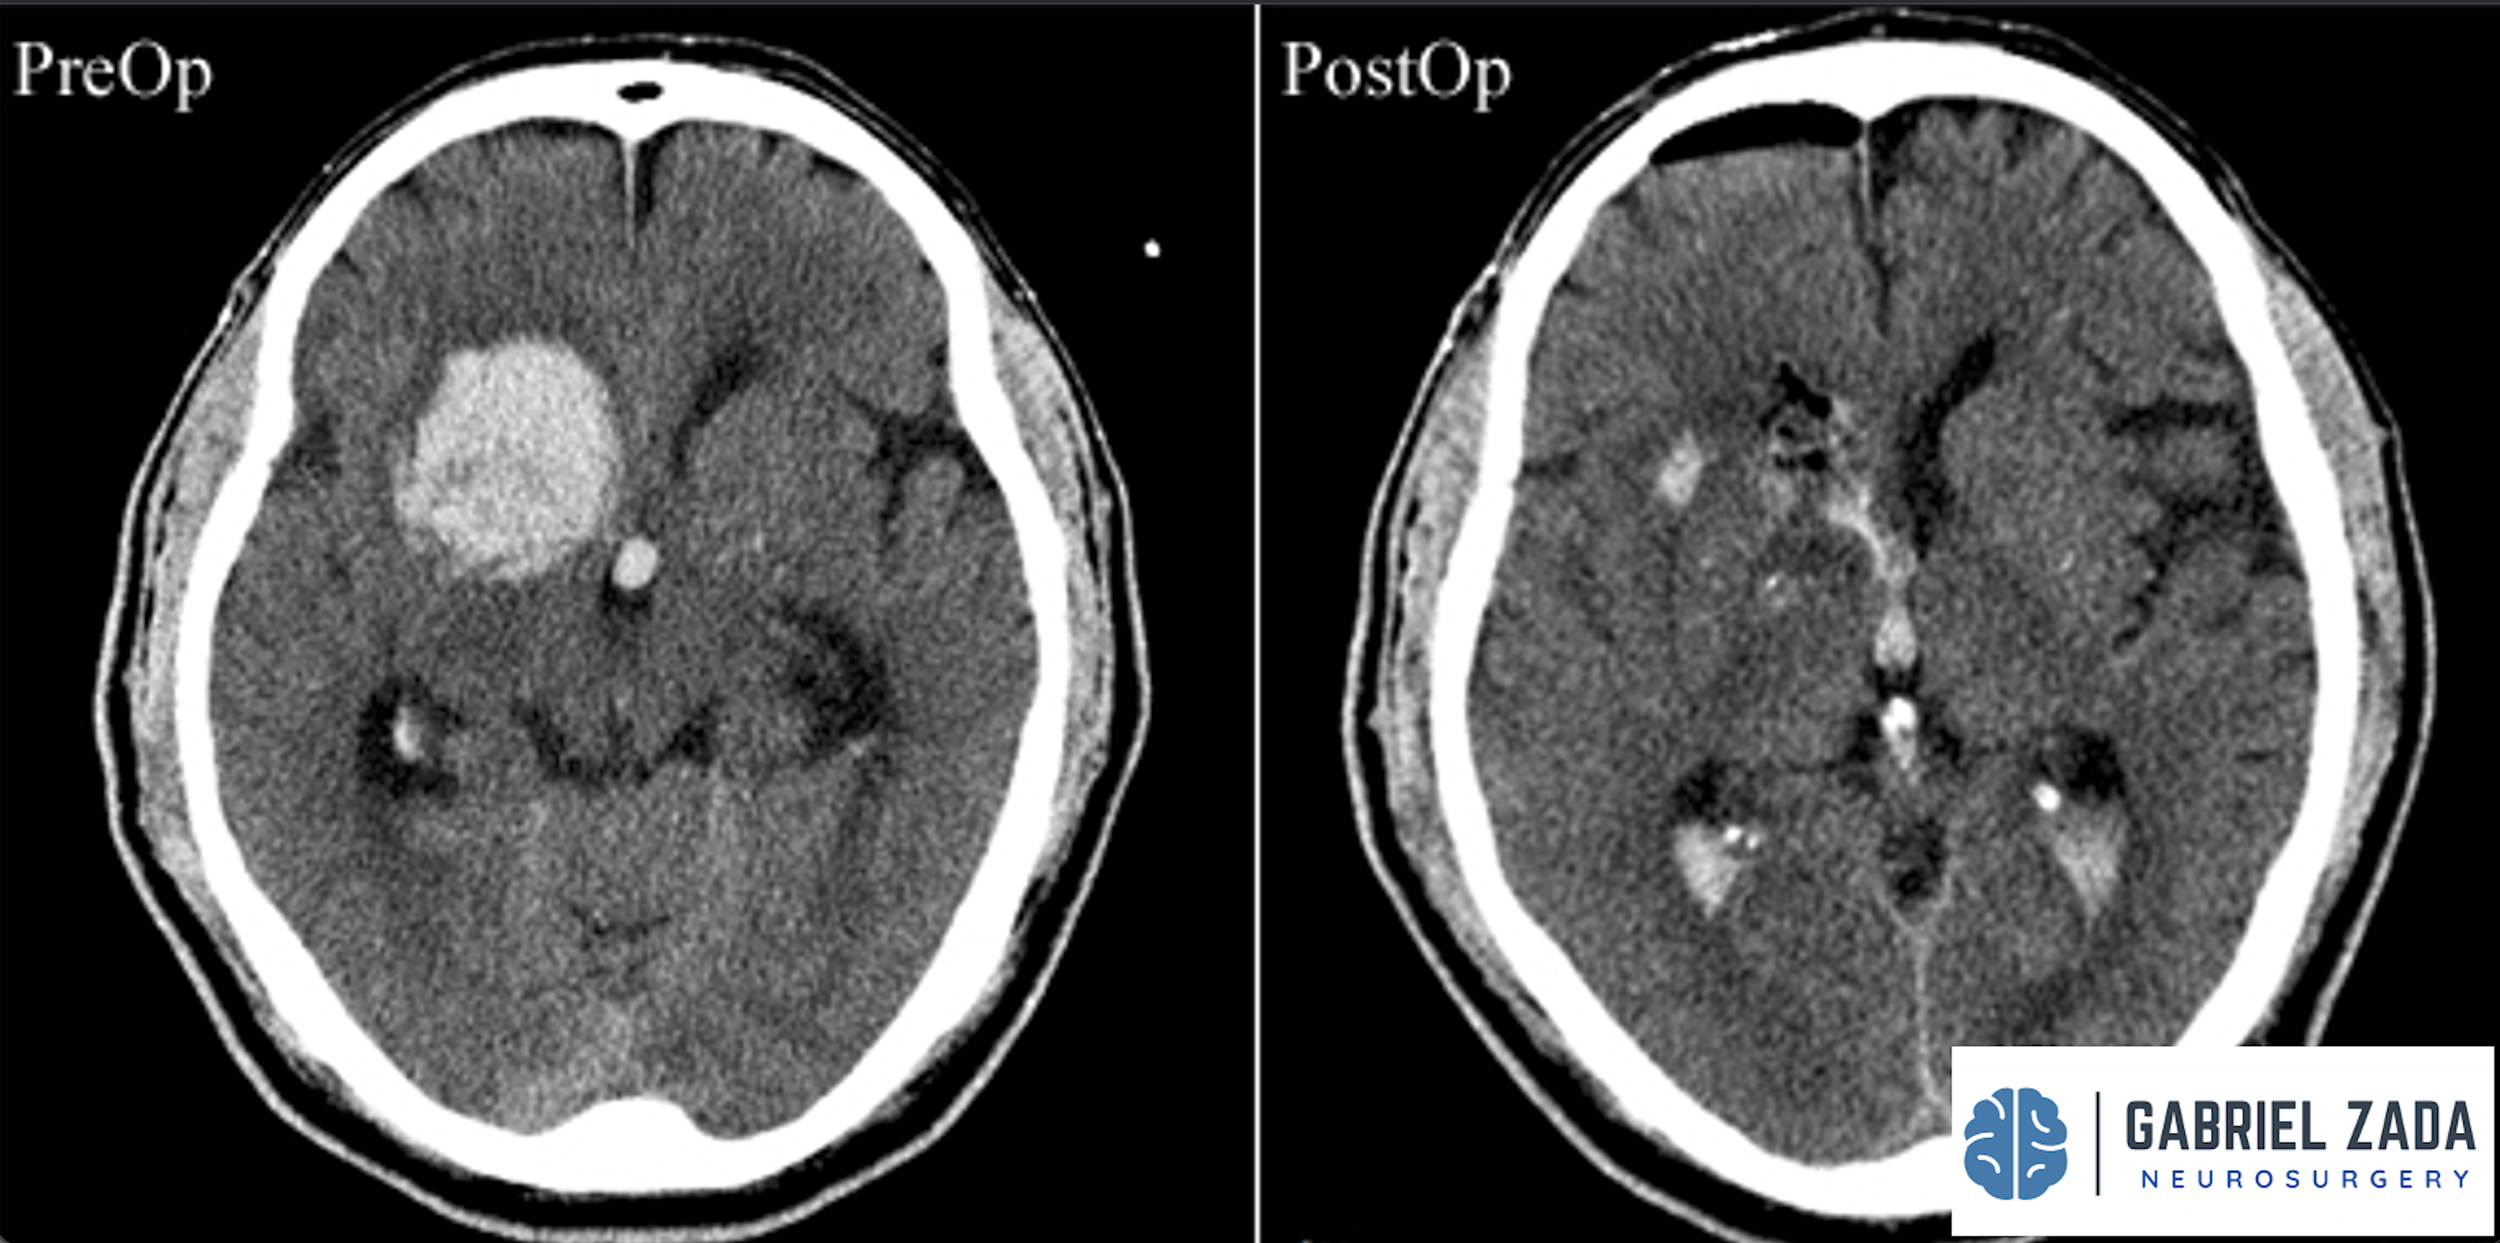

Explore this comprehensive gallery featuring pre‑ and post‑operative imaging of patients with skull‑base tumors treated by Gabriel Zada, MD, MS, FAANS, FACS. These cases highlight Dr. Zada’s expertise in advanced neurosurgical techniques and outcomes.

*Representative cases shown for educational purposes. All images de-identified. Individual results vary.